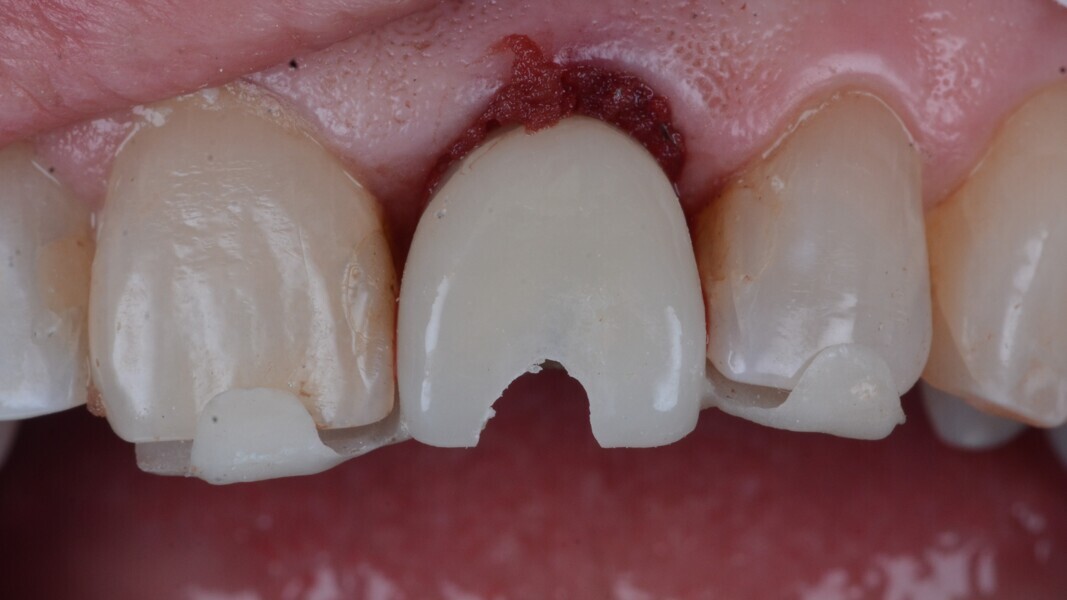

Fig. 12: Final implant position assessment in relation to gingival margins.

Fig. 11: Final implant position assessment.